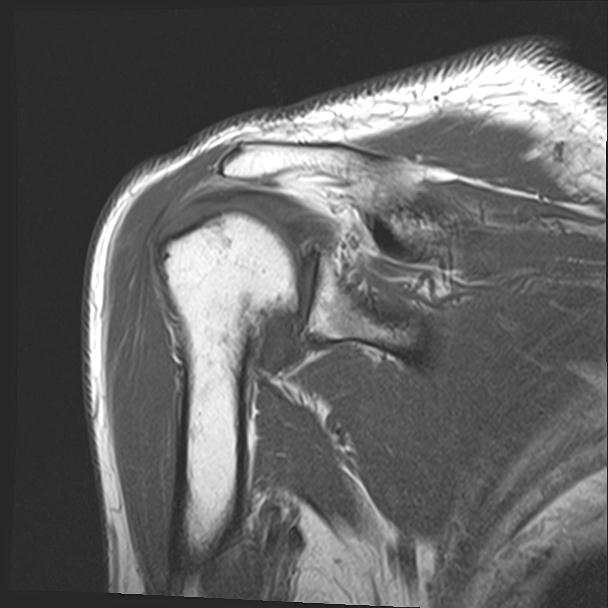

60058 3/9 11/4 右肩 2R+MRI 73歳男性 肩腱板損傷